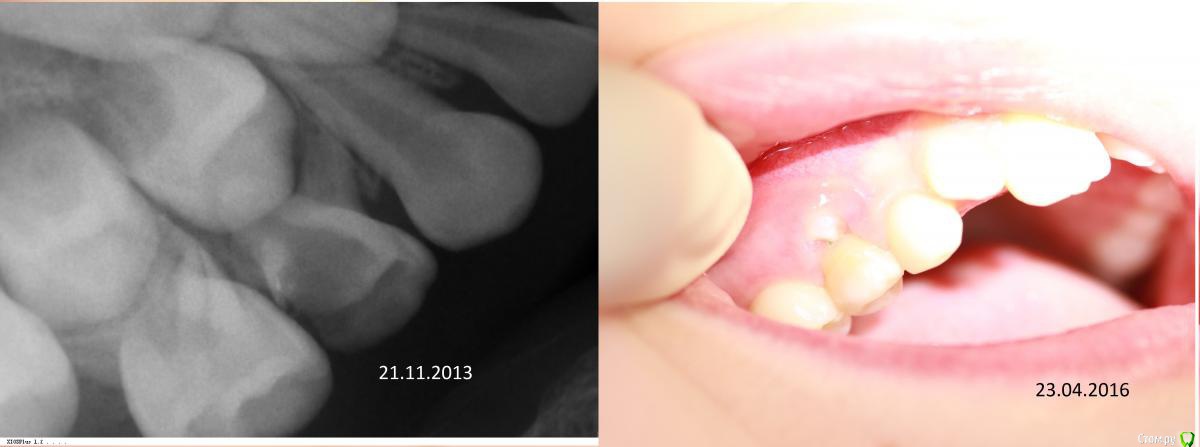

Джима Опубликовано 24 апреля, 2016 Поделиться Опубликовано 24 апреля, 2016 Девушки, вот читаю вас и думаю - прочитала бы года три-четыре назад, испугалась бы и не работала бы в каналах Вот, на ловца и зверь бежит, вчера сфоткала:карточка:снимка с каналами нет - далеко не всегда делаю.Ксан, завидую тебе белой завистью. К нам Небольсина не собирается Ссылка на комментарий

Джима Опубликовано 24 апреля, 2016 Поделиться Опубликовано 24 апреля, 2016 (изменено) буду теперь всех своих мимопроходящих леченых периодонтитов фоткать, если буду успевать. да, бывают неудачи, но совсем редко, т-т-т.чёт картинка растянутая получилась, ну да бог с ней. Изменено 24 апреля, 2016 пользователем Джима Ссылка на комментарий

Kota Опубликовано 24 апреля, 2016 Поделиться Опубликовано 24 апреля, 2016 Девушки, вот читаю вас и думаю - прочитала бы года три-четыре назад, испугалась бы и не работала бы в каналах Вот, на ловца и зверь бежит, вчера сфоткала:IMG_1949.JPGкарточка:Маслова0001.JPGснимка с каналами нет - далеко не всегда делаю.Ксан, завидую тебе белой завистью. К нам Небольсина не собирается честно говоря такой бы зуб и я попыталась бы спасти. свищ только у мезиального корня. шансы на благоприятный прогноз есть. а в случае снимка автора, то воспаление между корнями и шанс минимальный. я в свое время на эти межкорневые кисты насмотрелась. Ссылка на комментарий